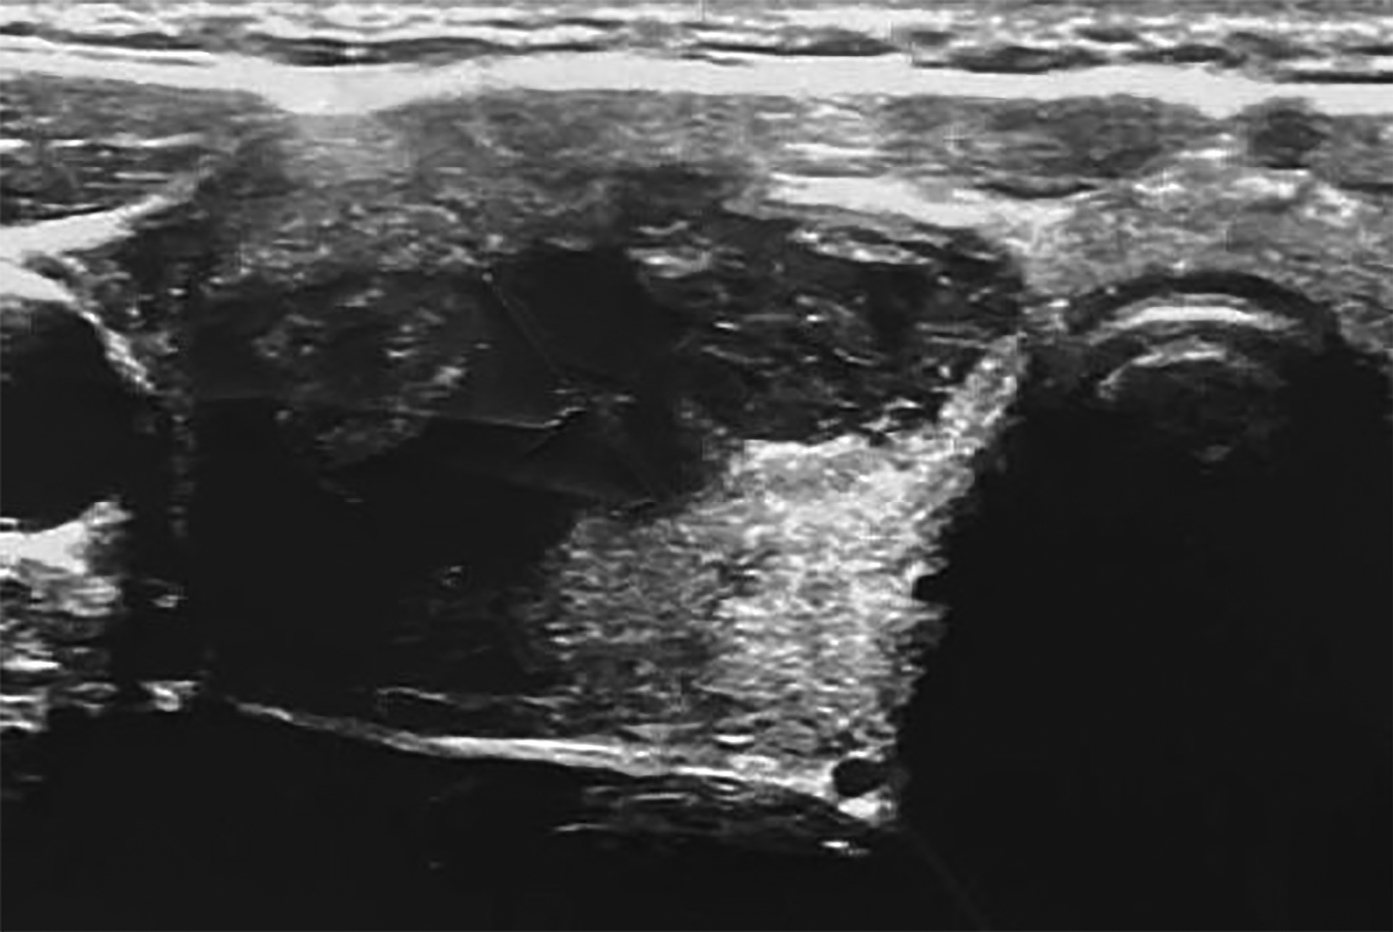

11. Рисунок 11. УЗИ-картина узлового образования правой доли щитовидной железы до начала лечения.

Тема

Тип Прочее

Посмотреть (481KB)

Метаданные ▾